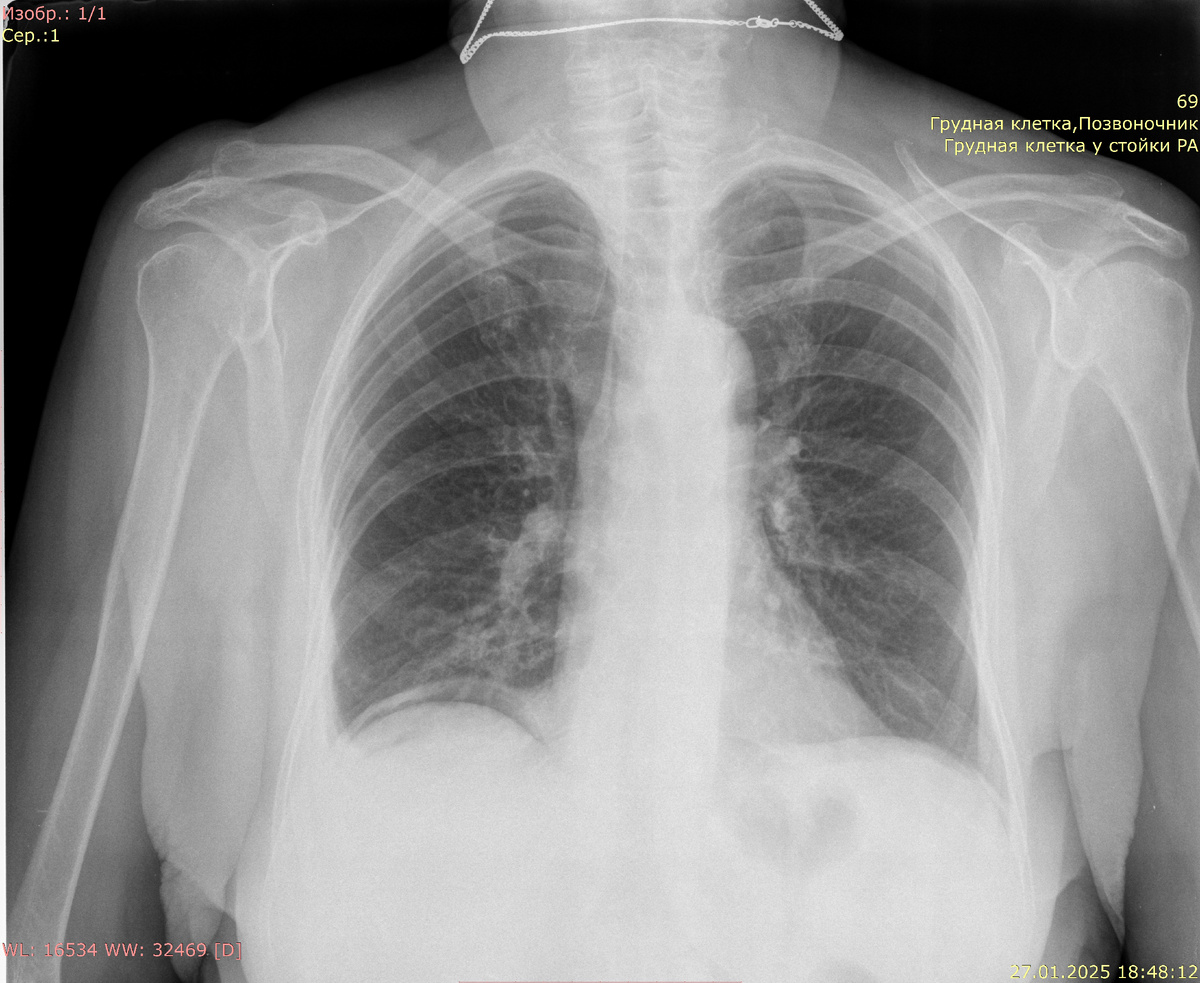

При перфорации полого органа, такого как кишечник или желудок, воздух может накапливаться под диафрагмой, что визуализируется на рентгенограммах в виде пузырьков газа. Эта находка обычно указывает на необходимость неотложной хирургической помощи, так как она может сигнализировать о высокой степени угрозы для жизни пациента. На рентгенологических изображениях свободный газ проявляется как области с пониженной плотностью, чаще всего расположенные под правым или левым куполом диафрагмы. Это связано с анатомическими особенностями расположения органов в брюшной полости, где газ имеет тенденцию подниматься к верхним участкам.